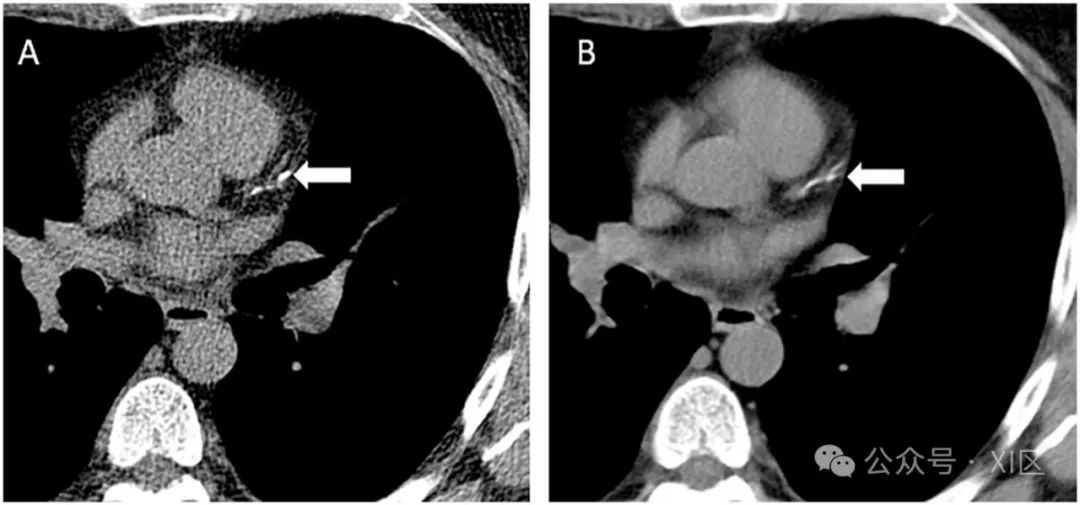

(A) 钙评分CT显示在一名62岁无症状男性中,钙评分小于100,根据Framingham风险评分为中等风险。所有的钙沉积都位于左前降支冠状动脉的近端(箭头所示)。在完成初步的非门控胸部CT后,没有必要重复进行钙化评分CT,正如(B)所示,因为多项研究表明非门控胸部CT的定性评分(轻微,如图B所示,箭头)与定量Agatston评分之间有极佳的相关性。